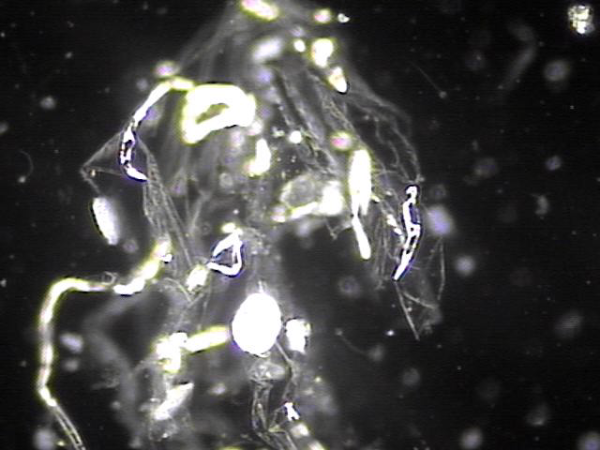

주 2회 전립선의 표적 치료후 배출된 상피세포의 현미경학적 사진입니다.

A microscopic image of epithelial cells expelled after twice-weekly targeted prostate therapy.